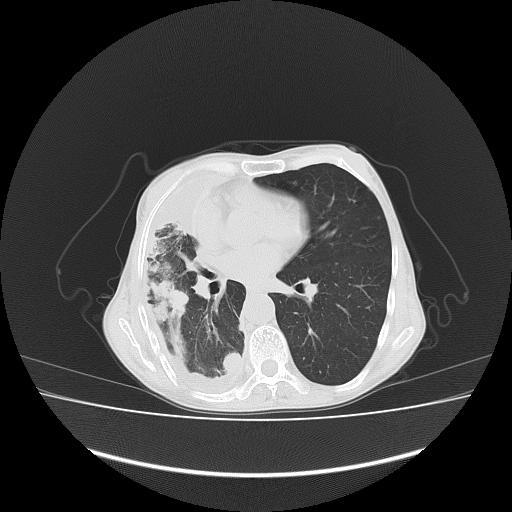

标题: CT16930:女 59 胸痛6个月 胸水脱落细胞学见瘤细胞 [打印本页]

标题: CT16930:女 59 胸痛6个月 胸水脱落细胞学见瘤细胞

可见多发肺内病灶,且胸膜病灶较多有圆球状而非丘状,多考虑胸膜转移瘤伴胸腔积液,右侧胸廓缩小固定,且部分病灶呈丘状,尚不除外恶性胸膜间皮瘤伴肺内转移

恶性胸膜间皮瘤伴肺内转移可能性大;或胸膜、肺内均为转移瘤,左肺下叶亦见多发小结节影。

右侧胸廓塌陷,右侧胸膜广泛增厚并见多发胸膜结节,右侧少量胸腔积液并包裹。

胸膜转移瘤  包裹性胸腔积液  肺内转移

右胸腔结节均考虑来自胸膜(部分来源于叶裂),考虑胸膜间皮瘤或转移瘤.